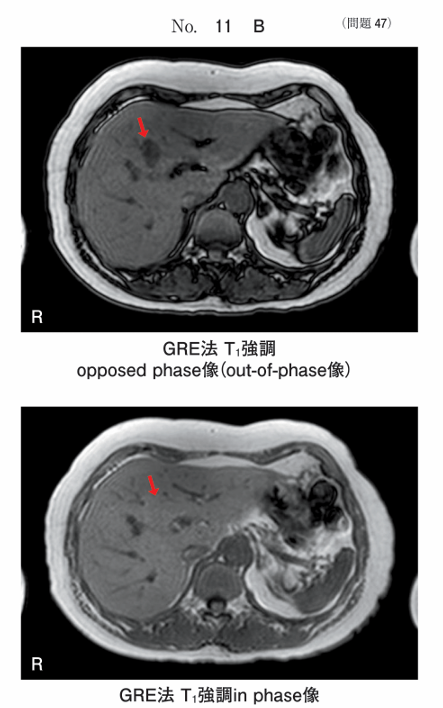

午前/問題47

同一腫瘍の超音波画像別冊No. 11AとMR像別冊No. 11Bを別に示す。矢印の腫瘤の主成分はどれか。

1.水

2.血液

3.脂肪

4.線維

5.カルシウム